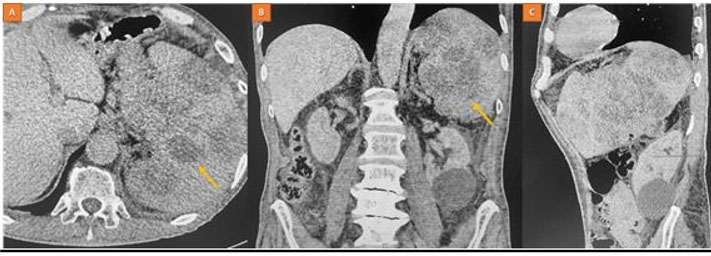

A particular form of inflammatory pseudotumor of the lung: The plasma cell granuloma

Keywords: Inflammatory pseudotumor, Lung, Plasma cell granuloma